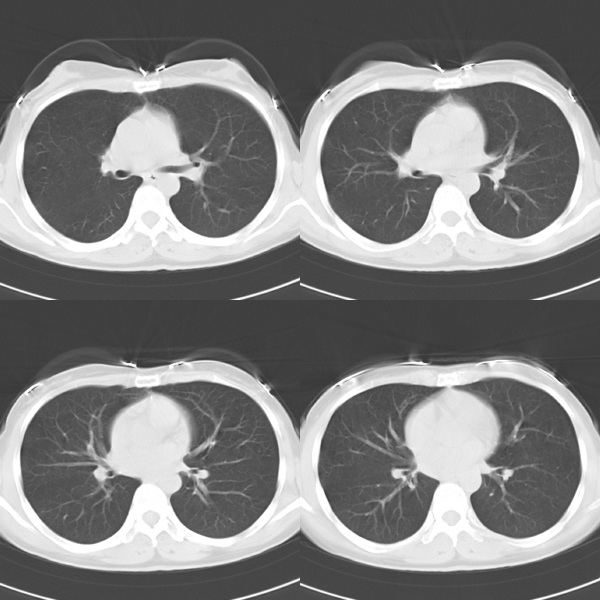

标题: CT19623:F40y,肋骨改变。

40岁女性,双侧胸部疼痛,以左侧为明显1+年。余无明显异常。

左侧肋骨骨纤维异常增殖症,

骨囊肿?

左侧肋骨单发膨胀性病变,皮质连续,病史较长,首先考虑良性病变:骨纤可能性大。